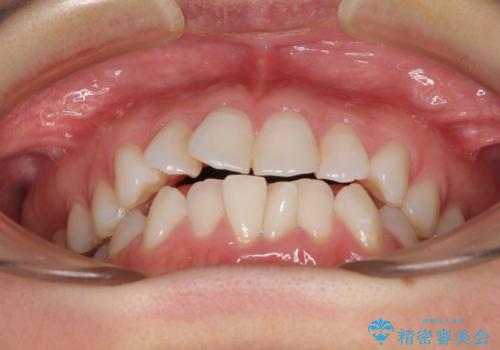

- ワイヤーではない矯正治療があると聞いたとのことで来院された患者様です。

長年前歯のデコボコを気にしていたもののワイヤー矯正に抵抗があり躊躇していたそうですが、インビザラインなら治療してみたいとのことで相談にいらっしゃいました。

インビザライン適用の歯列であったため、歯と歯の間を削るIPRを用いて改善することとしました。

下顎前歯の叢生が顕著な場合、歯列改善後に歯と歯と歯肉の間にブラックトライアングルという隙間ができてしまいます。

軽減することはできますが、完全に解決することは矯正治療のみでは不可能なため、リスクとして事前に周知しておく必要があります。